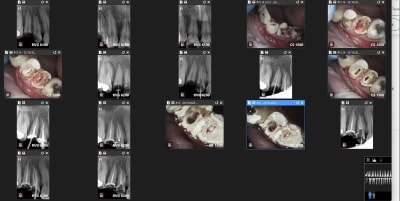

Comparaison des traitements de 2 praticiens différents au même tarif. Même patient 16 26. Pourquoi se faire chier aucun souci sur 26. ,

--------

> Allez avec un crampon de digue sinon ça fait désordre. -)

rien a redire sur les endos de chicot

neanmoins la question de gabzou concernant le % de cas réellement difficiles est intéressante car chicot tu illustres ce propos par des cas que tu dois trouver emblématiques datant de 2019/2020

j'ai pris au pif. sinon plus récent. je ne les capture pas toutes.

Indépendamment du reste, il y a clairement une racine MV non traitée dont on distingue le canal, ce qui est l'anatomie standard d'une 26.

Conclusion, le praticien l'a sciemment ignorée pour aller plus vite.

On peut discuter de la rémunération, des raisons qui ont amené ce praticien à choisir de bâcler le travail, mais il est indiscutable que le praticien ne peut pas avoir ignoré avoir fait n'importe quoi.

Je parle pas mal confraternité aux étudiants et leur explique qu'il ne faut pas critiquer le travail des autres (en tout cas pas devant les patients) car nous n'étions pas là lorsqu'il a été fait et qu'il peut y avoir des difficultés qui ne sont pas forcément visibles au premier abord.

Dans un cas comme celui ci, j'avoue que j'ai quand même du mal à trouver une raison qui explique çà en dehors du je-m'en-foutisme.

J'ai bien précisé que tout n'est pas facile. Cette 26 l'est, je n'ai quasiment aucun doute.